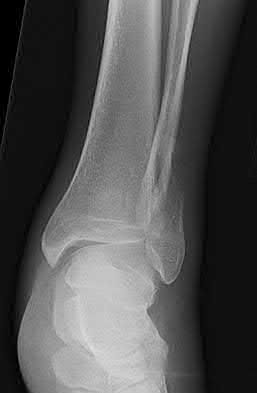

Question 2:

A 28-year-old male sustains a severe hyper-dorsiflexion injury to his ankle in a motor vehicle accident, resulting in a Hawkins Type III talar neck fracture. Which of the following arteries provides the predominant blood supply to the body of the talus, placing it at significant risk for avascular necrosis in this injury?

Correct Answer: Artery of the tarsal canal

Explanation:

The artery of the tarsal canal, which is a branch of the posterior tibial artery, provides the dominant blood supply to the talar body. In a Hawkins Type III fracture (talar neck fracture with subtalar and tibiotalar dislocation), the blood supply from the artery of the tarsal canal, the artery of the sinus tarsi, and capsular vessels are disrupted, leading to an avascular necrosis (AVN) rate approaching 100%.